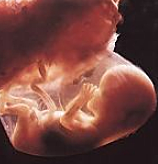

• Semana 12

Semana 12

El bebé ya se mueve dentro de la mujer y ya es capaz de estirarse y dar pequeñas pataditas. Si es el primer embarazo aún es pronto para que las mujeres noten esta sensación de hormigueo . Pero las mujeres que ya tienen su segundo embarazo ya pueden sentir esta sensación alrededor de las 12 semanas. Él bebe ya puede tener 10 semanas de vida y mide 6,5 centímetros y pesa 18 gramos. Él bebe ya se pude alimentar a través del cordón umbilical, recibiendo ya nutrientes y oxigeno